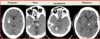

MRI findings of hepatic encephalopathy

Hepatic encephalopathy (like alcoholic cirrhosis) => b/l, symmetric hyperintense lesions of the basal ganglia, most comonly in the globus pallidus